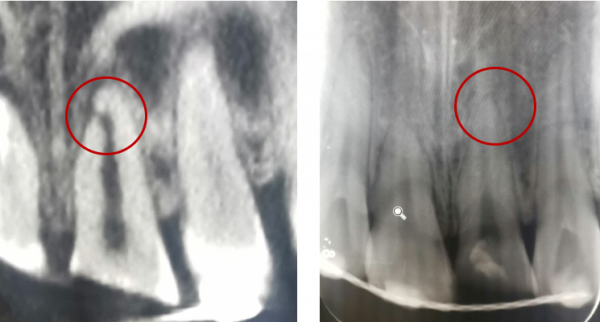

冠根折:累及牙釉質--牙本質--牙骨質折斷,累及牙釉質--牙本質--牙骨質--牙髓折斷

治療方案:方案(1)正畸或外科牽引4mm+冠延長+根管治療+樁核冠修復或根面覆蓋;方案(2)拔除患牙後種植修復;方案(3)意向性再植;方案(4)自體牙移植。